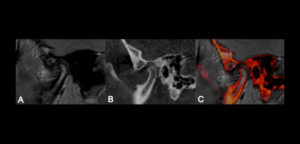

En los pacientes desdentados, que requieren una prótesis completa ya sea convencional o implanto soportada, los dientes artificiales se colocan en la prótesis completa por